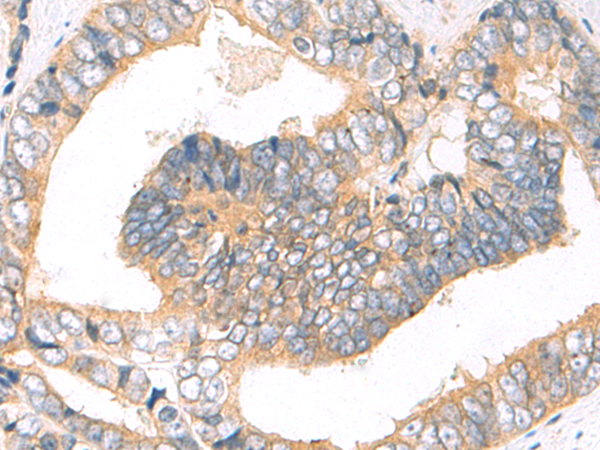

IHC positive control: |

Human lymphoma and human breast cancer |